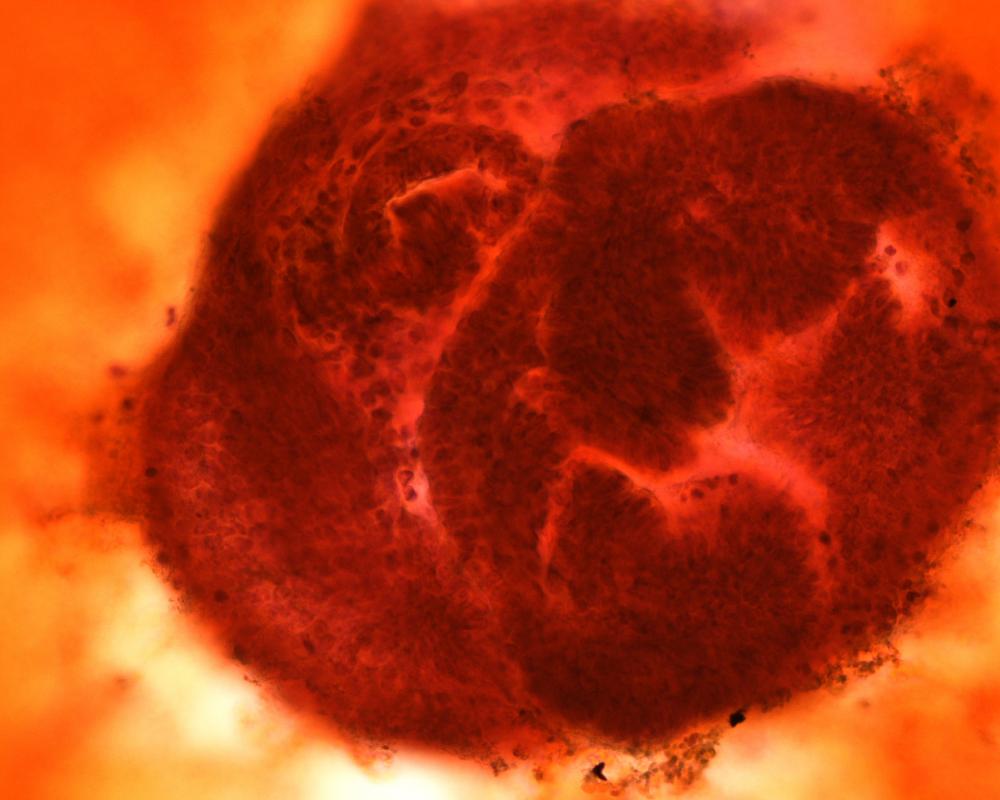

第34回日本臨床細胞学会九州連合会学会(長崎)スライドカンファレンス症例5

種別:体腔液

出題:琉球大学医学部附属病院 松本 裕文 先生

| 年齢 | 77歳 | 性別 | 男性 |

| 採取部位 | 胸水 | 採取方法 | 穿刺吸引法 |

| 検体処理法 |

既往歴:気管支喘息

現病歴:1カ月持続する咳嗽,息切れを主訴に精査目的で来院.右下肺野の透過性低下,両側胸水貯留,縦隔から鎖骨上窩にかけてリンパ節腫大を認めた。

| 正解 | 3.悪性リンパ腫 |

| 1.腺癌 | 35件 | (36.1%) | |

| 2.悪性中皮腫 | 11件 | (11.3%) | |

| 3.悪性リンパ腫 | 45件 | (46.4%) | |

| 4.反応性中皮細胞 | 6件 | (6.2%) | |

| 5.扁平上皮癌 | 0件 | (0.0%) | |

| 投票総数 | 97件 | (100%) |